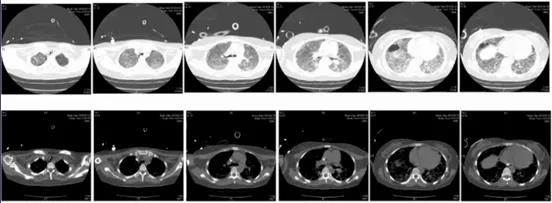

图4 患者胸部CT(2019-02-18)

2月15日,患者D-二聚体水平升高至35.2 mg/L(我院检查上限值),纤维蛋白原消耗明显,患者多部位出血,更换膜肺(图3),之后患者出凝血障碍得到一定程度的缓解(表10)。此段时间患者氧合有明显改善,考虑撤离ECMO。2月18日胸部CT提示大部分呈修复、纤维化表现,右下肺肺大泡可能与机械通气时间长、肺损伤愈合等有关(图4)。单用VV-ECMO期间,患者潮气量和分钟通气量逐渐升高,氧合改善,故于2月20日撤离ECMO,但患者当天晚间出现气胸。